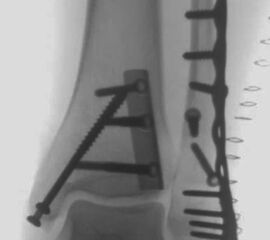

Die Versorgung von AO 44-B Frakturen erfolgt über einen längsverlaufenden lateralen Zugang. In der Regel gelingt eine suffiziente Stabilisierung mittels interfragmentärer Zugschraube (bei langem Frakturverlauf ggf. 2 Zugschrauben) und einer zusätzlichen Neutralisationsplatte (Abbildung 9 & 10).

Bei multifragmentären Frakturen (AO 44-B2.3) oder bei schlechter Knochenqualität sollte die Versorgung mittels winkelstabiler Plattenosteosynthese erwogen werden (Abbildung 11 & 12).

Seit einer Untersuchung von Nelson und Jensen aus dem Jahre 1940 wird allgemein akzeptiert, dass die Indikation zur Osteosynthese des Tibiahinterkantenfragments nur dann besteht, wenn die Größe mehr als ein Drittel (nach zahlreichen Autoren auch ein Viertel) der Gelenkfläche beträgt (Abbildung 15) 25. Dieses bis heute allgemeinakzeptierte Vorgehen basiert auf der Beobachtung von lediglich acht unterschiedlich versorgten Patienten. Seither gibt es keine weiteren klinischen Studien, die dieses Vorgehen stützen. Mittlerweile gibt es allerdings zunehmend Hinweise, dass bei der Versorgung des posterioren Malleolus viele andere Faktoren eine wichtige Rolle spielen 26. Da an der Tibiahinterkante das Lig. tibiofibulare posterius ansetzt (Abbildung 16), wird durch die offene Reposition und Stabilisierung die Integrität und die physiologische Spannung der hinteren Syndesmose rekonstruiert (Abbildung 17). Dies ist entscheidend für die anatomische Reposition der Fibula in der Tibiainzisur.

Gardner et al. konnten beispielsweise zeigen, dass die offene anatomische Reposition der Tibiahinterkante der Stabilisierung mittels Stellschraube überlegen war und gleichzeitig mit einer geringeren Rate an postoperativen Fehlstellungen der Fibula in der CT-Kontrolle einherging 2728. Aus Sicht der Autoren ist prinzipiell die Stabilisierung über eine direkte Reposition indiziert, wenn die Größe des Fragmentes dies erlaubt. Bei gleichzeitigem Vorliegen einer Fraktur des lateralen und/oder medialen Malleolus sollte zunächst die Versorgung der des Tibiahinterkantenfragments erfolgen. Dies erlaubt die radiologische Kontrolle der Reposition und Osteosynthese-Lage, welche durch eine zuvor aufgebrachte Fibula-Platte häufig erschwert ist 29. Dafür werden die Patienten in Seitenlage gelagert. Dies erlaubt die direkte Versorgung der posterioren Malleolusfraktur über einen posterolateralen Zugang 30. Das sehr kräftige Periost wird im Frakturverlauf inzidiert und aus den Frakturspalt entfernt, so kann eine anatomische Reposition erfolgen. Entsprechend der Fragmentgröße erfolgt entweder die Versorgung mittels Drittelrohrplatte in Antiglide-Technik oder eine Zugschraubenosteosynthese. Die Versorgung der Fibula-Fraktur gelingt über den gleichen Zugang. Zur Versorgung des medialen Malleolus wird der Patient auf den Rücken umgelagert. Dies kann bei entsprechender Vorbereitung ohne erneutes steriles Abdecken erfolgen. Durch dieses Vorgehen konnte im eigenen Kollektiv die Notwendigkeit einer Stabilisierung der Syndesmose mit Stellschraube/Tight Rope deutlich reduziert werden.